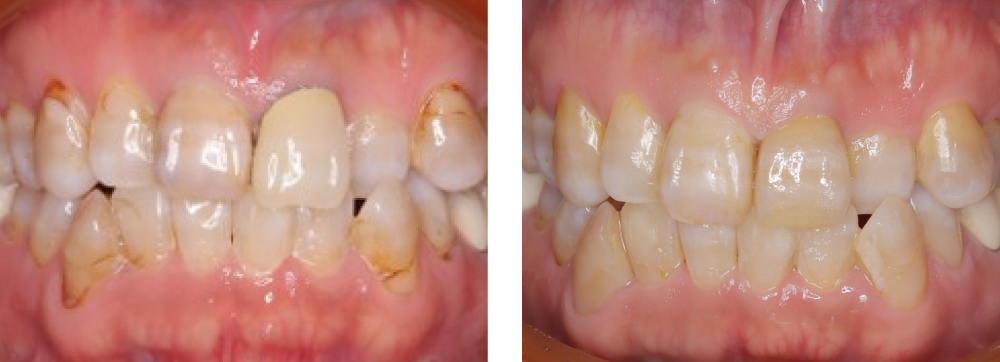

全顎保険治療

術前

術後

| 治療内容 | 全顎的に保険内で治療を行った |

|---|---|

| 治療期間・回数 | 約3年・約70回 |

| 費用 | 保険適用となります |